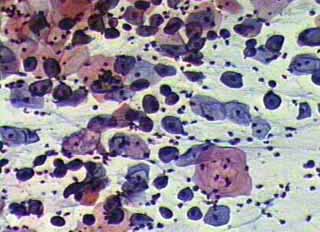

Ιατρικές Εικόνές - κυτταρολογικών επιχρισμάτων κατά Papanicoloau και η συσχέτιση τους με το ιστορικό

Το ενδιαφέρον του κλινικού γυναικολόγου στο πόρισμα του κυτταρολογικού επιχρίσματος του τραχήλου της μήτρας, περιορίζεται συνήθως στο συμπέρασμα του, σχετικά με την ύπαρξη κάποιας δυσπλασίας ή έστω φλεγμονής, στην περιοχή.

Ωστόσο ακόμη και το λεγόμενο ‘’φυσιολογικό’’ επίχρισμα, μπορεί να μας δώσει μία επί πλέον αξιόλογη πληροφόρηση, αν τα ευρήματα του ενταχθούν σωστά από τον κλινικό γιατρό, τόσο στην χρονική συγκυρία, όσο και στο ιστορικό, ή στα κλινικά, κολποσκοπικά και υπερηχογραφικά ευρήματα.

Η γενικότερη γυναικολογική οπτική γωνία, στην ερμηνεία ενός κυτταρολογικού πορίσματος, είναι αρκετά σημαντική για την αξιολόγηση άλλων προβλημάτων, πέραν των δυσπλασιών.

Οι εικόνες και τα πορίσματα που επιδεικνύονται, είναι τυχαία ευρήματα ενός απογευματινού ιατρείου.